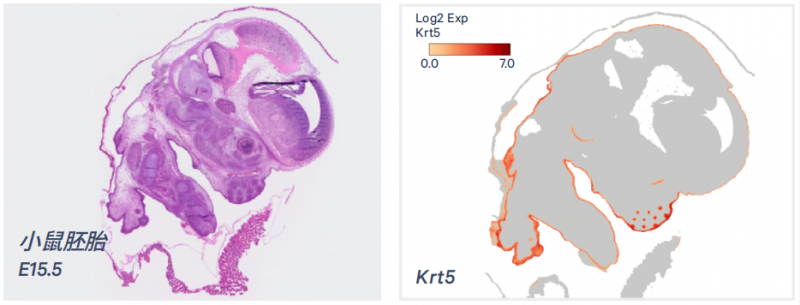

Visium HD 将强大的全转录组空间基因表达与单细胞尺度分辨率结合起来,来发现每一微米组织中独特的生物学特性。同时启用 CytAssist 仪器,让样本在简单的运行工作流中获得最好的数据。

▲全转录组、单细胞分辨率、连续覆盖

▲通过 Visium CytAssist 实现精准的转录本定位